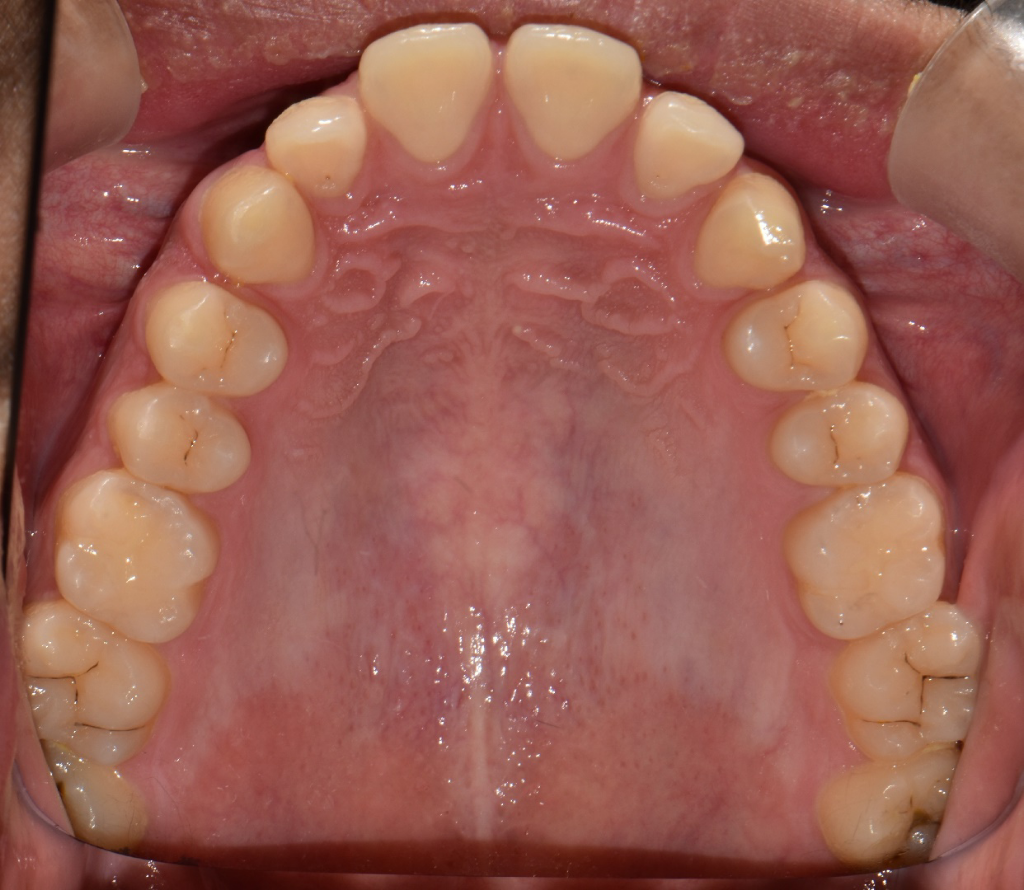

상기된 사진과 같은 치아상태에서 의사선생님이 국소적 법랑질우식이있으나 지켜보자했습니다. 헌데 요즘 게을러져서 한달 반정도를 4일에한번주기로 꼼꼼하게양치하고 치실질하는 식으로 했었는데요, 이것이 충치를 한달 반동안에 신경치료해야할만큼 위험하게 번질수도있나요?

21세 남성이고 3년간 안닦았다가 법랑질에 우식생긴이력이 있는지라 좀 우려스럽습니다

사진에서 보기에는 범랑질 표면에 살짝 표면충치가 생긴 것으로 보입니다. 범랑질 표면에 생긴 충치가 한달반 만에 상아질로 까지 진행될 가능성은 희박합니다.

충치가 교합면에도 잇고 치아 사이에도 충치가 잇는거 같습니다. 치료를 받으셔야될것같습니다.